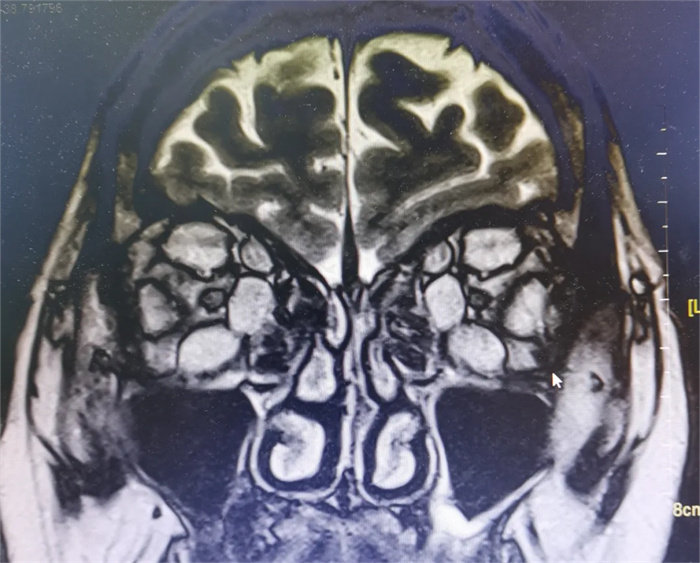

入院后完善眼眶MR等相關(guān)檢查發(fā)現(xiàn),鄒女士眼球旁的四條肌肉都明顯增粗,在眼眶內(nèi)相對(duì)狹小的空間內(nèi)對(duì)視神經(jīng)產(chǎn)生部分壓迫,還推擠著眼球向外凸出,如果再不進(jìn)行治療,可能會(huì)產(chǎn)生不可逆的視力下降,后果嚴(yán)重。

▲眼眶MR+增強(qiáng)影像結(jié)果